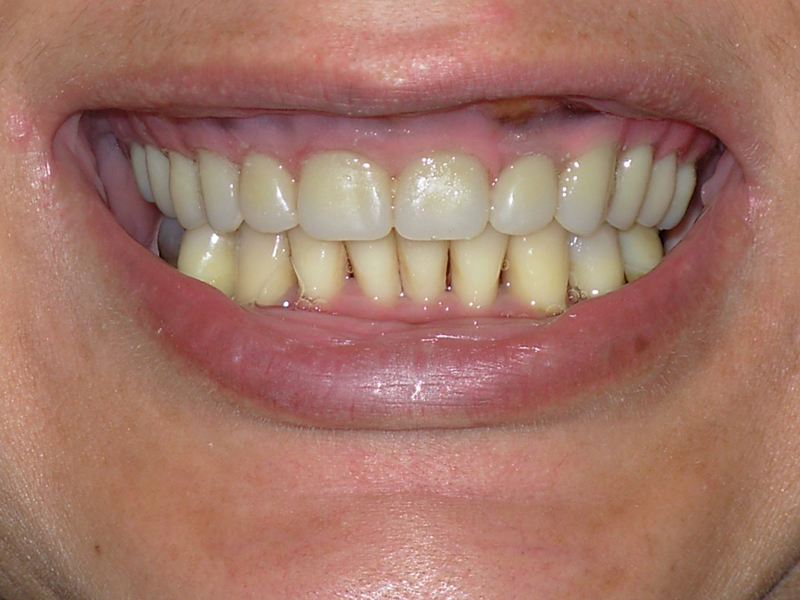

Na Clínica Pontes Odontologia, somos referência em implantes dentários em Fortaleza, oferecendo tratamentos de alta qualidade e tecnologia de ponta. Os implantes dentários são estruturas de titânio posicionadas cirurgicamente no osso maxilar ou mandibular para substituir as raízes dos dentes ausentes. Essa técnica permite a fixação de próteses personalizadas, restaurando a função mastigatória, a estética e a autoestima dos nossos pacientes.

Nosso compromisso é oferecer um tratamento de excelência, com profissionais especializados e tecnologia de última geração para implantes dentários em Fortaleza. Venha nos visitar e descubra por que a Clínica Pontes Odontologia é referência em implantes dentários em Fortaleza, devolvendo sorrisos e qualidade de vida aos nossos pacientes.